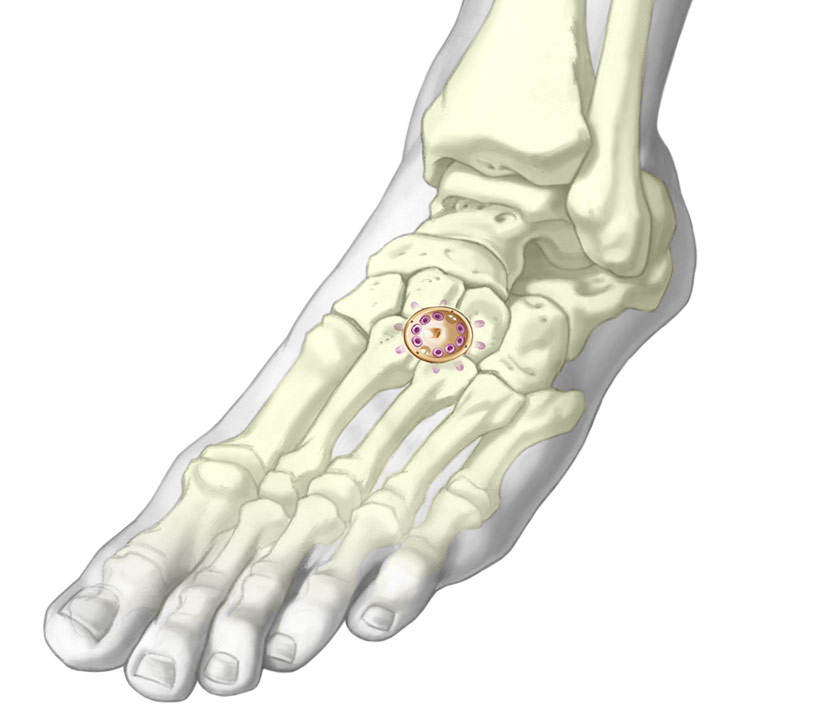

Usos comunes:

- Fusión de la articulación de Lisfranc

- Fusión de la articulación talonavicular

- Fusión de la articulación calcáneo-cuboidea

La PEEK Fusion Cup de TriMed se puede utilizar en procedimientos de fusión del metacarpiano y los metatarsianos.

- Fusione varios huesos del carpo o del tarso con una placa de puente de bloqueo de 360 grados avellanada